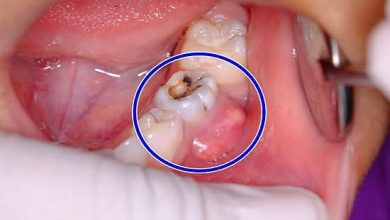

وصفات مذهلة لعلاج خراج الضرس( الأسنان) من المنزل ..وصفات لم تكن تعلمها

وصفات مذهلة لعلاج خراج الضرس( الأسنان) من المنزل ..وصفات لم تكن تعلمها تعتبر مشاكل الفم والأسنان من المشاكل الصحيّة التي…